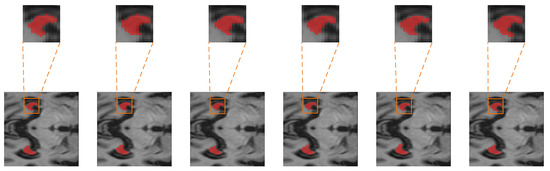

To show the hippocampus segmentation results of these algorithms more conveniently, the sagittal section, coronal section, and axial section segmentation results are provided in Figure 9, Figure 10, and Figure 11, respectively.

The first column shows sections of the three dimensions of the input MRI image (axial, sagittal, and coronal), along with the corresponding hippocampus segmentation labels. The 3D U-Net segmentation results are displayed in the second column. The segmentation results obtained by the Attention U-Net, UNETR, Swin UNETR, and CADyUNet models are shown in the third, fourth, fifth, and last columns, respectively. As illustrated in these figures, in contrast to the outputs of other algorithms, the outputs of the CADyUNet model are closer to the standard segmentation labels (particularly for marginal hippocampus segmentation), which proves the efficacy of CADyUNet in hippocampus segmentation tasks.